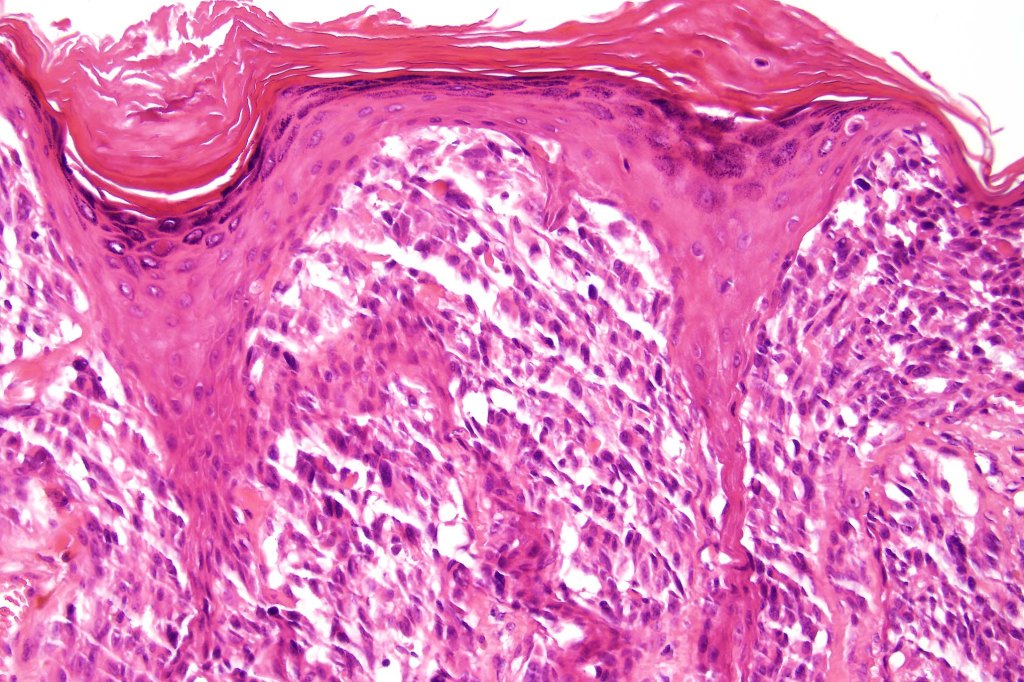

Combined common & deep penetrating nevus